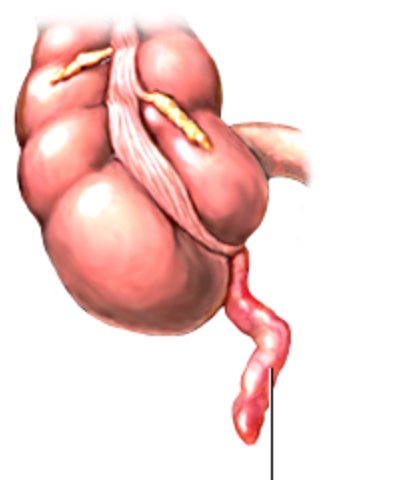

2. ANATOMÍA

1. Tubo ciego 2-20cm longitud, 3 a 6mm diámetro,con base en la confuencia tenias colónicas ciego

1. Irrigada x la arteria apendicular, colateral rama ileal arteria ileocólica, rama terminal arteria mesentérica sup.

1. Localización

1. Retrocecal 65%

1. Pélvica 30%